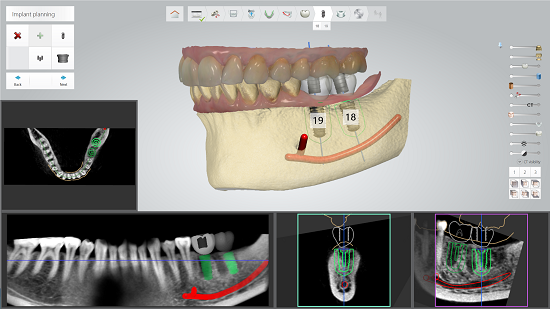

Copenhagen - 3Shape, a global leader in 3D scanners and CAD/CAM software solutions, has announced that dental professionals now can access the Biomet 3i family of implants in connection with 3Shape Implant Studio™.

Dentists, implantologists, and dental technicians access implant systems such as Biomet 3i when using Implant Studio software to assist in their implant planning.

“We are glad to add the Biomet 3i well-known and popular family of implant lines to the implant systems now available in connection with Implant Studio,” says Flemming Thorup, CEO at 3Shape. “Providing easy-access to leading implant systems like Biomet 3i is helping to make Implant Studio the industry’s most open and flexible solution for dental professionals.”